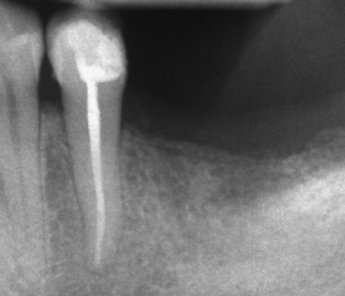

Добре пролекувани зъби

Ендодонтия